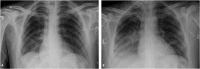

Epidemiology: The most frequent causes of acquired infection in the community that require admission to the ICU are respiratory infections, urinary tract infections and infections of the central nervous system. Among the infections acquired in the ICU, devices-associated infections are the most frequent.

Clinical manifestations: Depends on the location of the infection.

Diagnosis: It must be early due to its increased mortality.